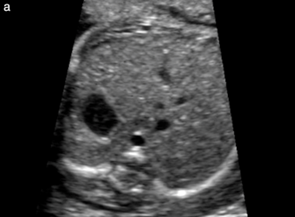

hydronephrosis